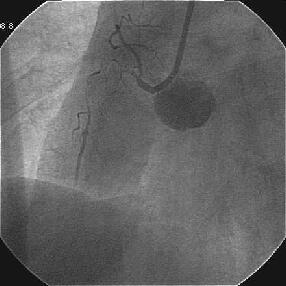

�ŏI�o���オ���IVUS�BIVUS��170507��septal���}����170509������2mm��O��

���̕����B

|

|

|

|

������������������������������������������������������������������������